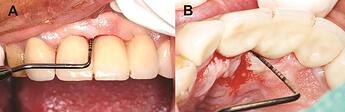

Peri-implant mucositis inflammation

Peri-implant mucositis demonstrating soft-tissue inflammation.

Peri-implantitis Clinical Manifestation

Peri-implantitis: ( A ) clinical photograph, ( B ) radiograph showing bone loss around an implant, and ( C ) clinical photograph showing buccal bone loss.